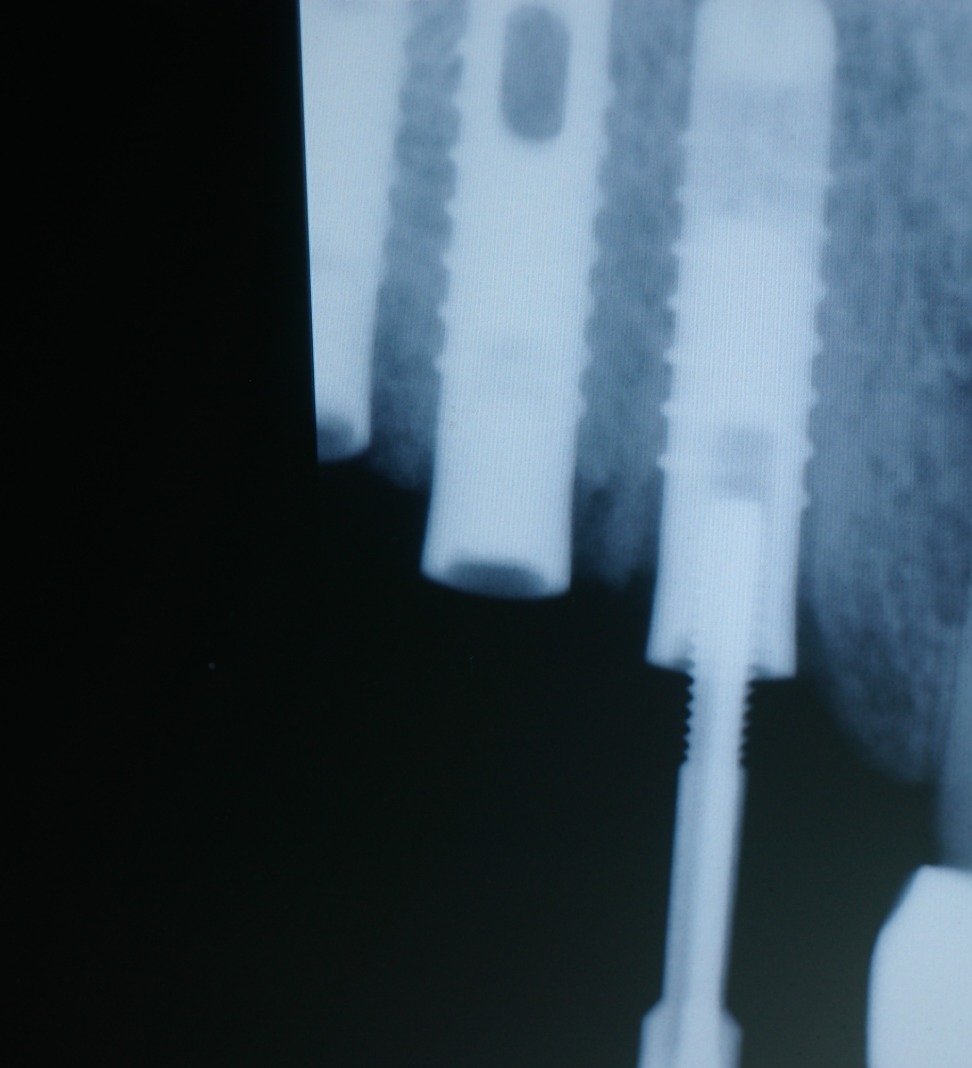

Actualmente vuelve el paciente de nuevo con la misma prótesis. Había roto dos de los tres pilares en concreto los más distales. El primero de los dos había roto la rosca del aditamento dentro del implante como ocurre habitualmente. Pero el ultimo pilar había roto directamente la cabeza del implante tal como se ve en la radiografía y lo que quedaba era un cilindro de titanio macizo perfectamente integrado en el maxilar, sin posibilidad de enroscar nada. Le explicamos al paciente que habría que quitar y poner un implante en el mismo acto. El paciente dijo que no, así que decimos que no se haría cirugía. Buscamos solución alternativa: hacemos un un agujero en el centro del macizo cilíndrico del implante roto y pasamos sucesivamente el set de machos roscantes. Utilizamos una fresa cañón de 1 mm que poco a poco se va introduciendo hasta 8mm con un poco de vagación, que hace que sea un poco mas de 1mm de diámetro. Posteriormente pasamos el conjunto de machos roscantes de métrica 2mm para poder usar un aditamento experimental, que era un palo de rosca de diámetro 2 mm unido a un cuerpo metálico en forma de sombrero napoleónico fabricado en cromo/cobalto, prototipos primitivos de la sistemática ASATIM y que tienen la característica de tener gran resistencia a la fractura. Nos llevó un tiempo largo el tallado de dichos aditamentos, tal como se puede observar en las imágenes, y tras cicatrizar la encía se le hizo una prótesis estándar. Esperemos que no lo rompa más veces.